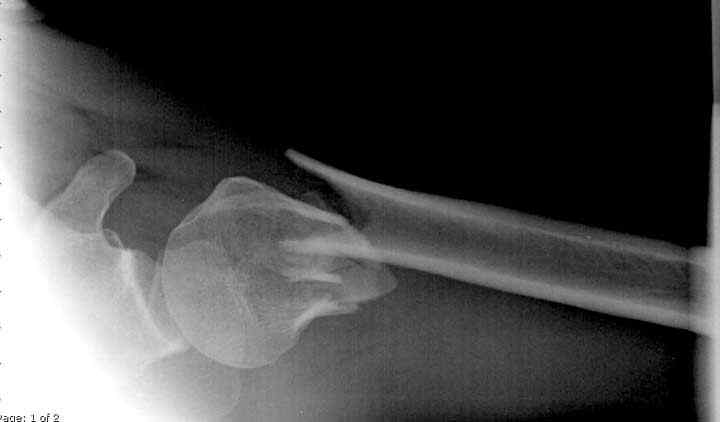

Пациентка Б.1953 г.р., врач-терапевт. Травма 27.11.08г. Падение с высоты роста. Выявлен закрытый не осложненный оскольчатый перелом хирургической шейки левого плеча со смещением. 02.12.08г. оперирована. Выполнена открытая репозиция и остеосинтез пластиной LCP Деост с дополнительной фиксацией отдельно лежащего фрагмента винтом. Послеоперационный период протекал без особенностей, заживление раны первичным натяжением. Швы сняты через 10 дней. Иммобилизация левой верхней конечности клиновидной подушкой 4 недели. По окончании срока – рентген-контроль и умеренная разработка плечевого сустава. В течении месяца функция левого плечевого сустава восстановилась удовлетворительно: поднятие руки до 110 гр., отведение - 90 гр. и до 110 гр. отведение с лопаткой. Отведение руки назад – 20 гр. Наружная и внутренняя ротация – 20 гр. Пациентка по настоянию самостоятельно вышла на работу. 27.03.09 при контрольном осмотре жалоб не предъявляет, болевой синдром в левом плечевом суставе отсутствует. Отведение плеча активно до 90 гр, пассивно с лопаткой до 110 гр., поднятие – 110 гр, отведение назад 20 гр, наружная и внутренняя ротация по 20 гр. На контрольных рентгенограммах отмечается смещение металлоконструкции, ротация головки плеча с приведением дистального отломка на 13 гр. и смещением к зади на 30 гр. Рентгенограммы прилагаются. Ваш взгляд на дальнейшую тактику лечения пациентки?

Нет аксиальной проекции сразу после вмешательства. Возможно, никакого значительного смещения нет, все осталось так, как первично сопоставили...и,

Уважаемый Евгений, похоже, что первый и второй Р-снимки выполнены несколько в разных положениях(ротация) плечевой кости, в связи с этим создается впечатление смещения пластины. Остеосинтез выполнен при угловом смещении отломков.Таковым и остался. Данная ситуация была бы очевидна гораздо раньше, если бы при контрольной Р-графии были выполнены снимки в 2-х проекциях.(Не в обиду, сам иногда выполняю только один).

Здесь пример открытой репозиции 57 летнего с переломом плеча (1,2) смещение обнаружено на интероперационном снимке. При нормальной прямой проекция (3) угловое смещение обнаружили в аксиальной проекции (4)